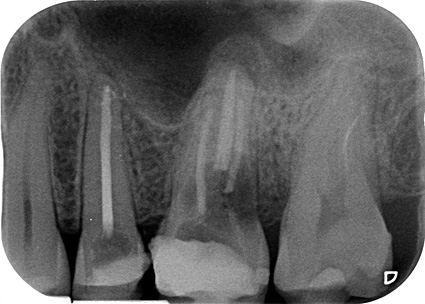

Una radiografía periapical forma parte de las denominadas radiografías intraorales, es decir, aquellas que se realizan mediante la colocación de placas radiológicas de diferente tamaño dentro de la boca, con el fin de obtener imágenes completas de uno o dos dientes y estudiarlo en su totalidad: ápice, corona, raíz, tejido óseo y espacio periodontal.